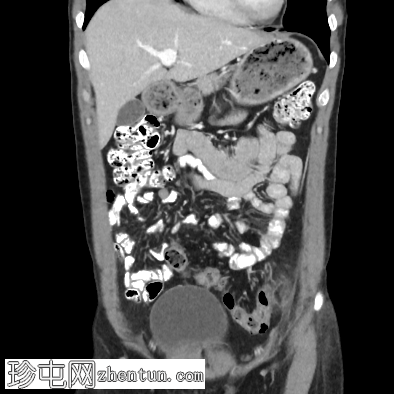

4.png

冠状位增强扫描(门静脉期)

乙状结肠-降结肠交界处前缘可见一卵圆形脂肪密度病灶,大小约20 x 7 mm(TR x AP)。病灶周围可见高密度环及脂肪条索影,符合大网膜垂炎的影像学表现。

CT扫描显示结肠旁有一小块卵圆形脂肪密度病灶,周围有薄层高密度环(“环状征”),并可见轻度脂肪条索影。未见肠壁增厚、脓肿形成或穿孔,排除了憩室炎等更严重的鉴别诊断。